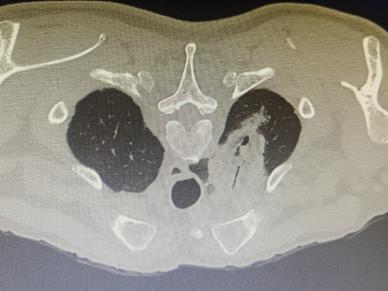

1.精准定位:医生通过CT影像锁定肿瘤位置,像导航一样精准规划“进攻路线”。

2.细针穿刺:用一根比笔芯还细的针,避开重要血管和器官,直达肿瘤“老巢”。